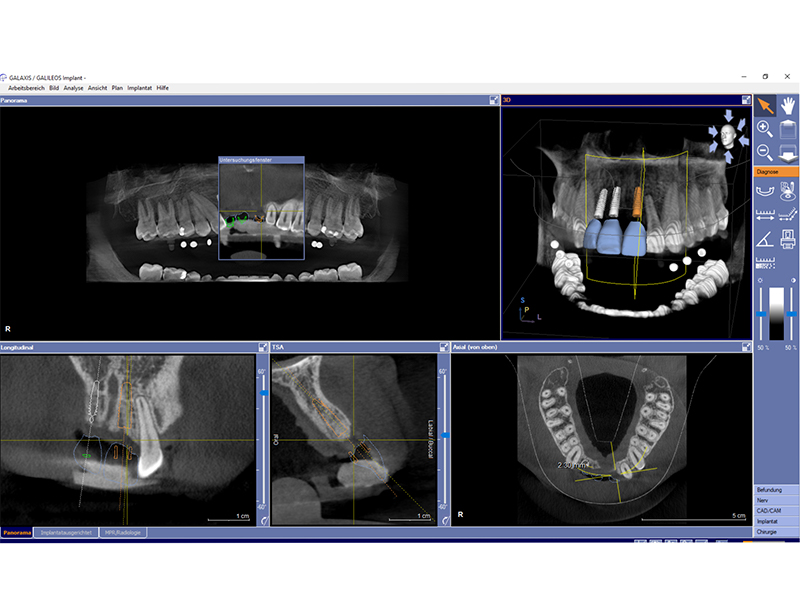

Zahnimplantate werden anhand von moderner virtueller 3D-Planung passgenau geplant und inseriert. Der Vorteil von Implantaten besteht darin, dass festsitzender ästhetischer Zahnersatz auch in solchen Fällen realisiert werden kann, in denen sonst nur herausnehmbare Prothesen möglich wären. Zudem ist im Gegensatz zur Brückenprothetik kein Beschleifen der Nachbarzähne notwendig.